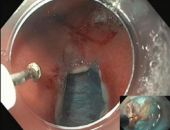

في إنجاز طبي مصري وعربي غير مسبوق، اختارت المجلة العلمية للجمعية الأمريكية للمناظير، حالة من مصر للنشر كغلاف لعدد يناير ٢٠٢٥ والحالة هي الأولى عالميا. ...